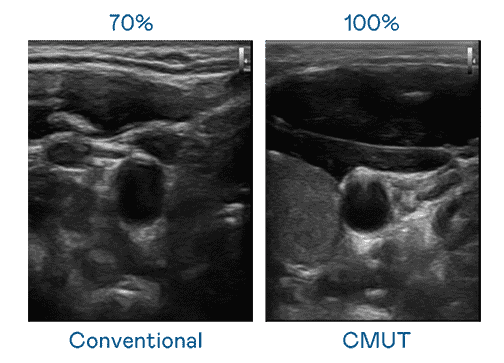

CMUT 技术是一种用电容式微机电元件来产生超音波讯号的技术。。。与传统 PZT 压电式技术相比,,,,CMUT 频宽增加 30%,,更宽频的超音波讯号让影像解析度大幅提升,,是实现高影像品质医疗超音波扫描、、、、促进精准医疗发展的关键技术。。。

大频宽带来超清晰影像

超音波影像的解析度高低,,,首先取决于探头能发出的讯号频宽。。银河集团 CMUT 可提供高清晰的超音波讯号,,,,提供高频宽、、、高灵敏度、、、、影像纹理细节更高的超音波影像,,,协助医护人员缩短影像判读时间及利用精准的医疗影像进行诊断。。。。